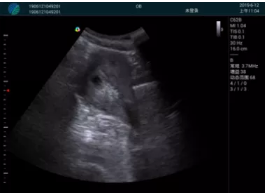

清晰顯示孕囊,通過軟件包計(jì)算孕齡7w+6d

M20實(shí)時(shí)引導(dǎo),術(shù)中清晰顯示孕囊被破壞和抽吸針的過程,清晰顯示吸引針

抽吸結(jié)束后縱切子宮,孕囊已被完全抽吸,未見明顯殘留

橫切子宮,發(fā)現(xiàn)右側(cè)宮腔靠近宮角處有少許脫模樣殘留

M20引導(dǎo)下,抽吸針找到右側(cè)宮角處再次清掃

二次抽吸后再次進(jìn)行超聲檢查,宮腔未見殘留,宮腔線清晰顯示